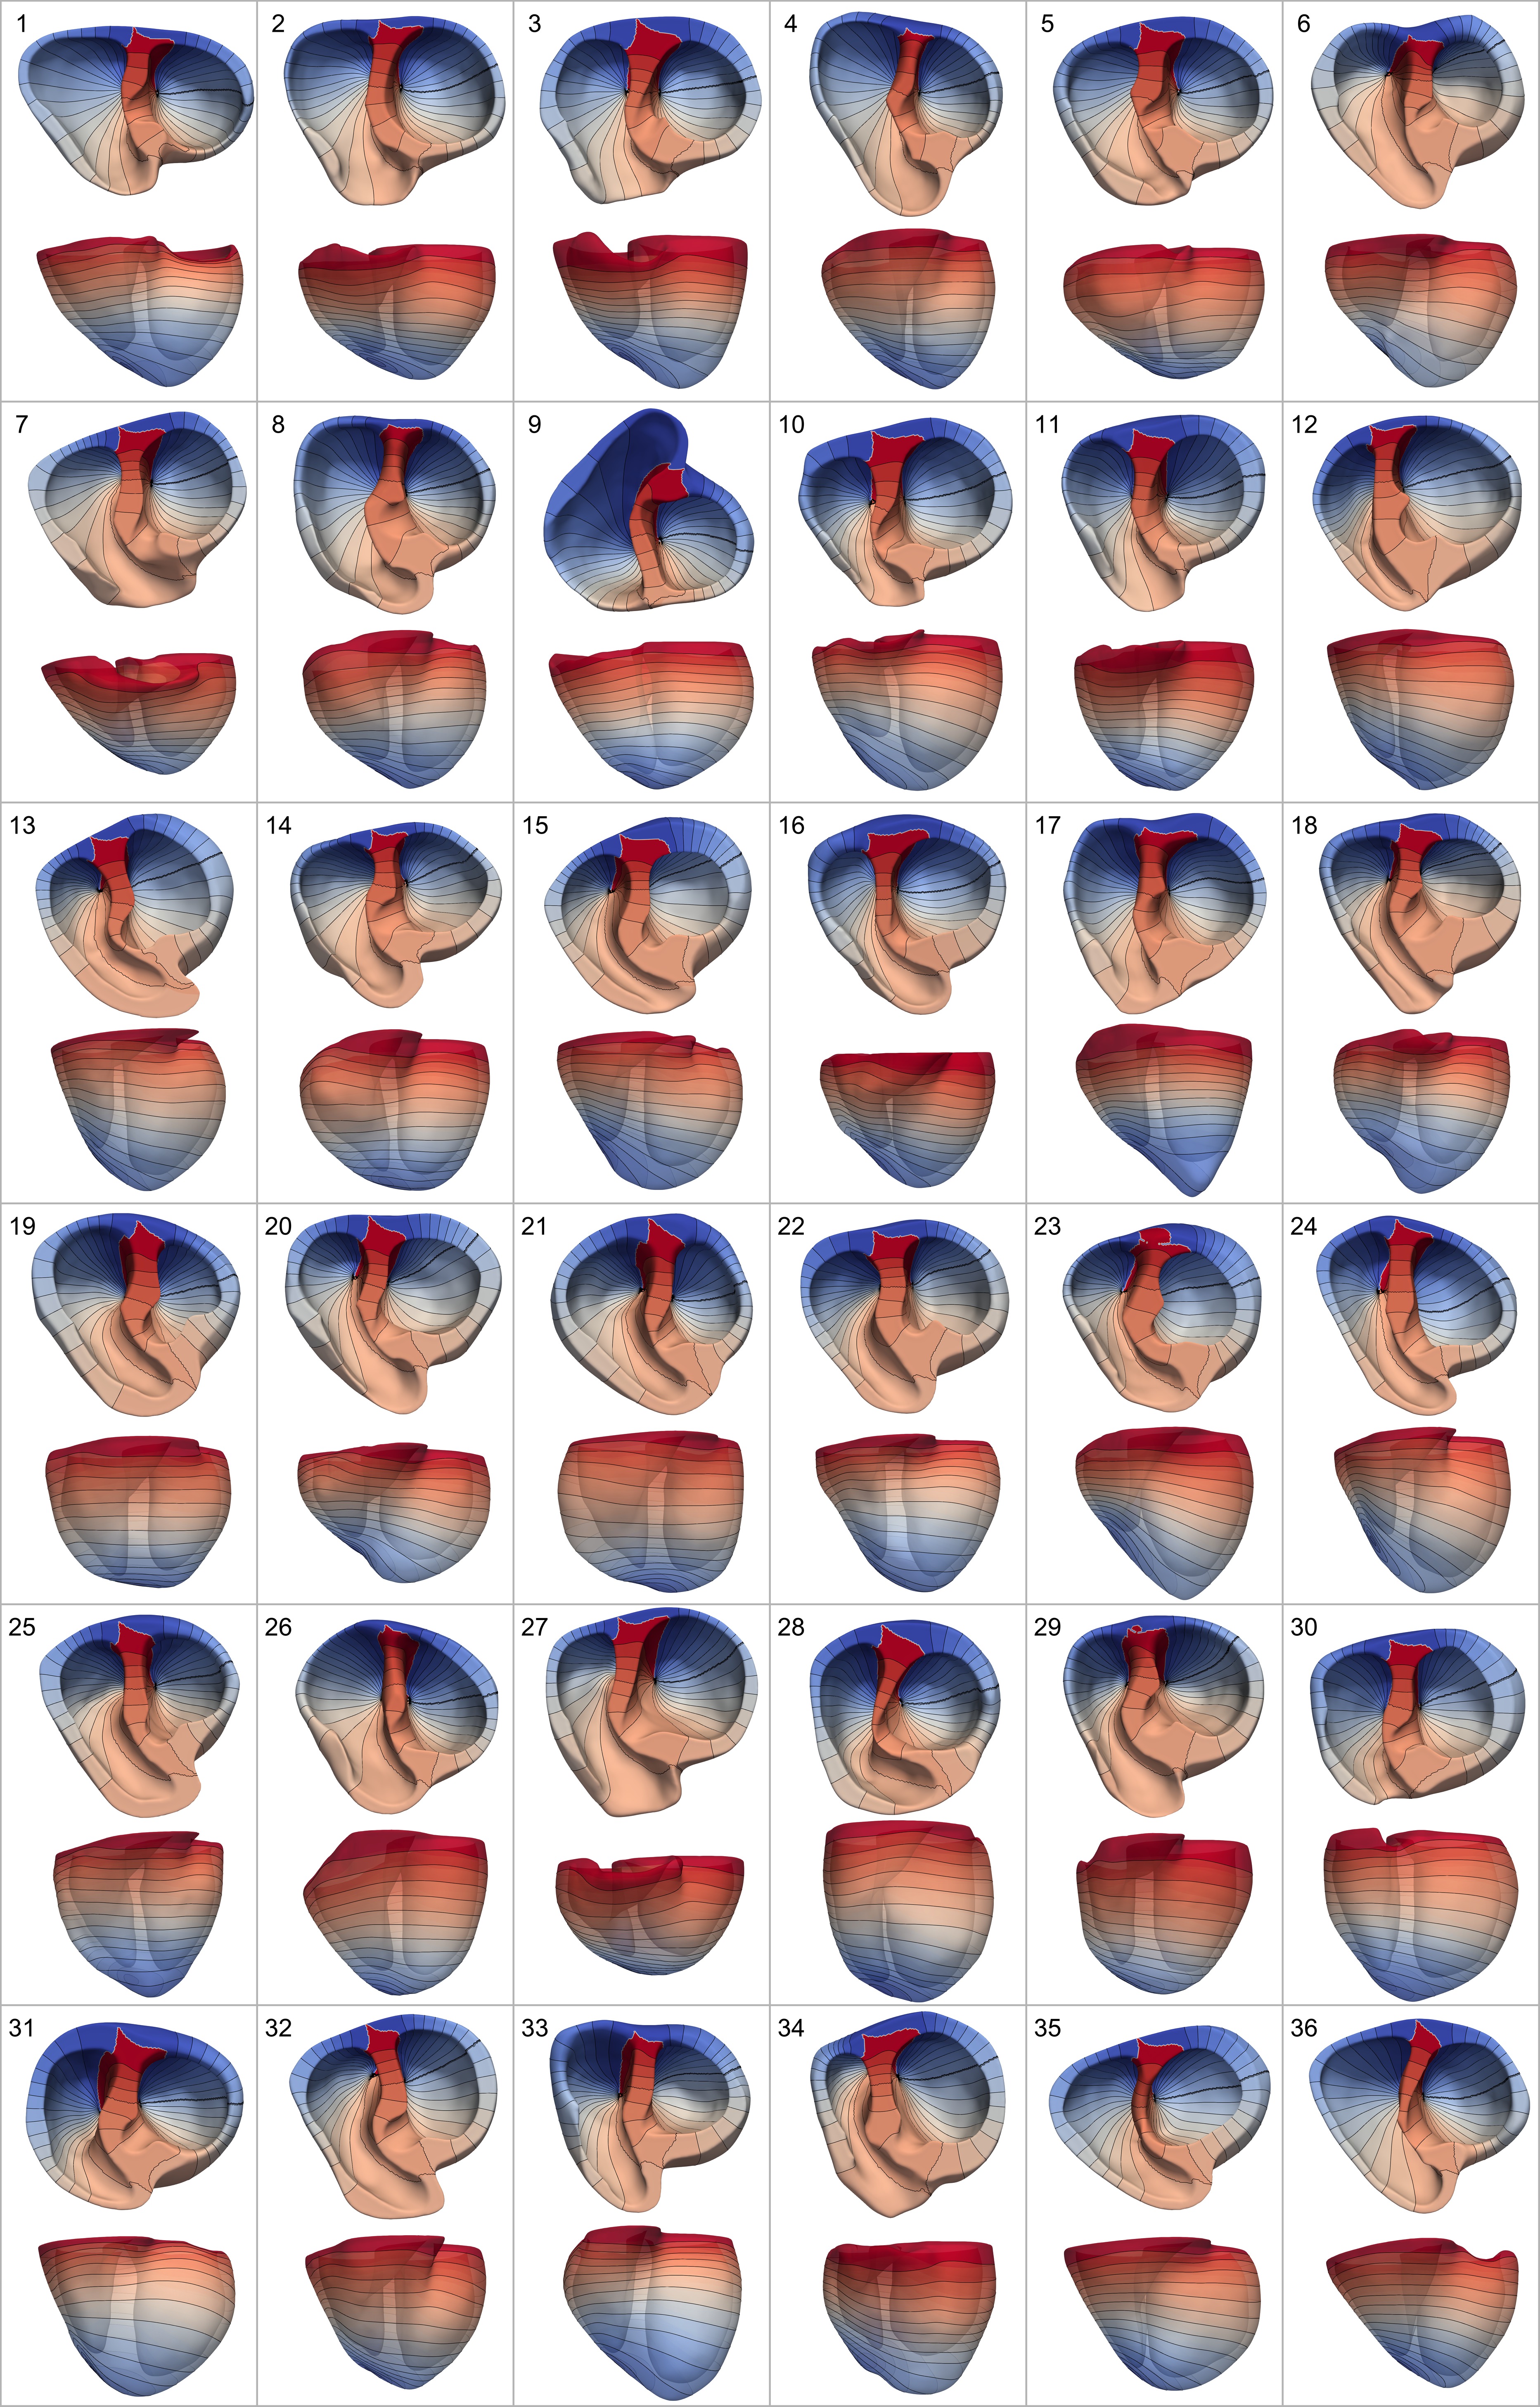

36 patient geometries were used for a comparison of Cobiveco and UVC under realistic conditions. These geometries were acquired as part of validation studies [23, 5] for electrocardiographic imaging (ECGI), which adhered to the Declaration of Helsinki and were approved by the Institutional Review Board of Almazov National Medical Research Center in Saint Petersburg, Russia. Written informed consent was obtained from each patient. Cardiac computed tomography (CT) images were obtained from patients with implanted pacemakers and segmented in a semi-automatic manner with the software of the Amycard 01C EP system (EP Solutions SA, Yverdon-les-Bains, Switzerland). As this system uses relatively coarse triangle meshes suitable for ECGI (edge lengths of 5 to 10 mm), they were first remeshed with Instant Meshes [18] and then tetrahedralized with Gmsh [12]. Some geometries included large parts of the aorta and the pulmonary artery. To yield consistent inputs for the computation of coordinates, we clipped all meshes at the base (where the LV outflow tract intersects the septal plane) and removed the bridge at the base of the RV. All 36 geometries are shown in Fig. S1 and mesh statistics are given in Table S1.

4.2 Visual comparison

Fig. 14 provides a visual comparison of Cobiveco and UVC for all four coordinates on the mean shape of the SSM and two exemplary patient geometries.

As the mean shape has a very uniform wall thickness, the contour lines of the rotational and apicobasal coordinates appear equidistant for both methods, but artifacts at the discontinuities of the rotational coordinate can be seen for UVC (green circles).

Patient 36 also has a relatively uniform wall thickness, but differences between both methods become more apparent. For UVC, the distance between contour lines of the rotational coordinate increases near the septal junctions (magenta vs. cyan circle), which is not the case for Cobiveco.

In patient 33, the differences are most pronounced. While the coordinates computed using Cobiveco still change very uniformly in space, there are substantial distortions in the UVC coordinates. The length of the segments between contour lines of the rotational coordinate changes up to four-fold between regions of small and large wall thickness. The apicobasal coordinate is also distributed very non-uniformly, indicating that the geodesic approach to normalize the apicobasal Laplace solution does not work reliably. In fact, a slight change of the geometry can cause a different geodesic path between apex and base to become the shortest and therefore lead to an abrupt change of the apicobasal coordinate. Taking a closer look at the transmural coordinate within the LV shows that it changes much faster at the endocardium than it does at the epicardium because the width of the region between the two boundary surfaces increases with the circumference.

If the coordinates always showed the same distortions for every geometry, this would only be a minor problem. However, comparing the rotational and apicobasal UVC coordinates for patient 33 and the mean shape reveals that the same coordinate values can represent quite different anatomical regions (yellow stars). In contrast, the coordinates obtained using Cobiveco are consistent across the geometries (green stars).

For pictures showing Cobiveco and UVC coordinates on all 36 patient geometries, the reader is referred to Fig. S1 and S2, respectively.

S1 Results on all patient geometries

Table S1 provides mesh statistics for the mean shape of the statistical shape model and the patient geometries. Rotational and apicobasal coordinates computed with Cobiveco on all 36 patient geometries are depicted in Fig. S1. Corresponding UVC coordinates are shown in Fig. S2.